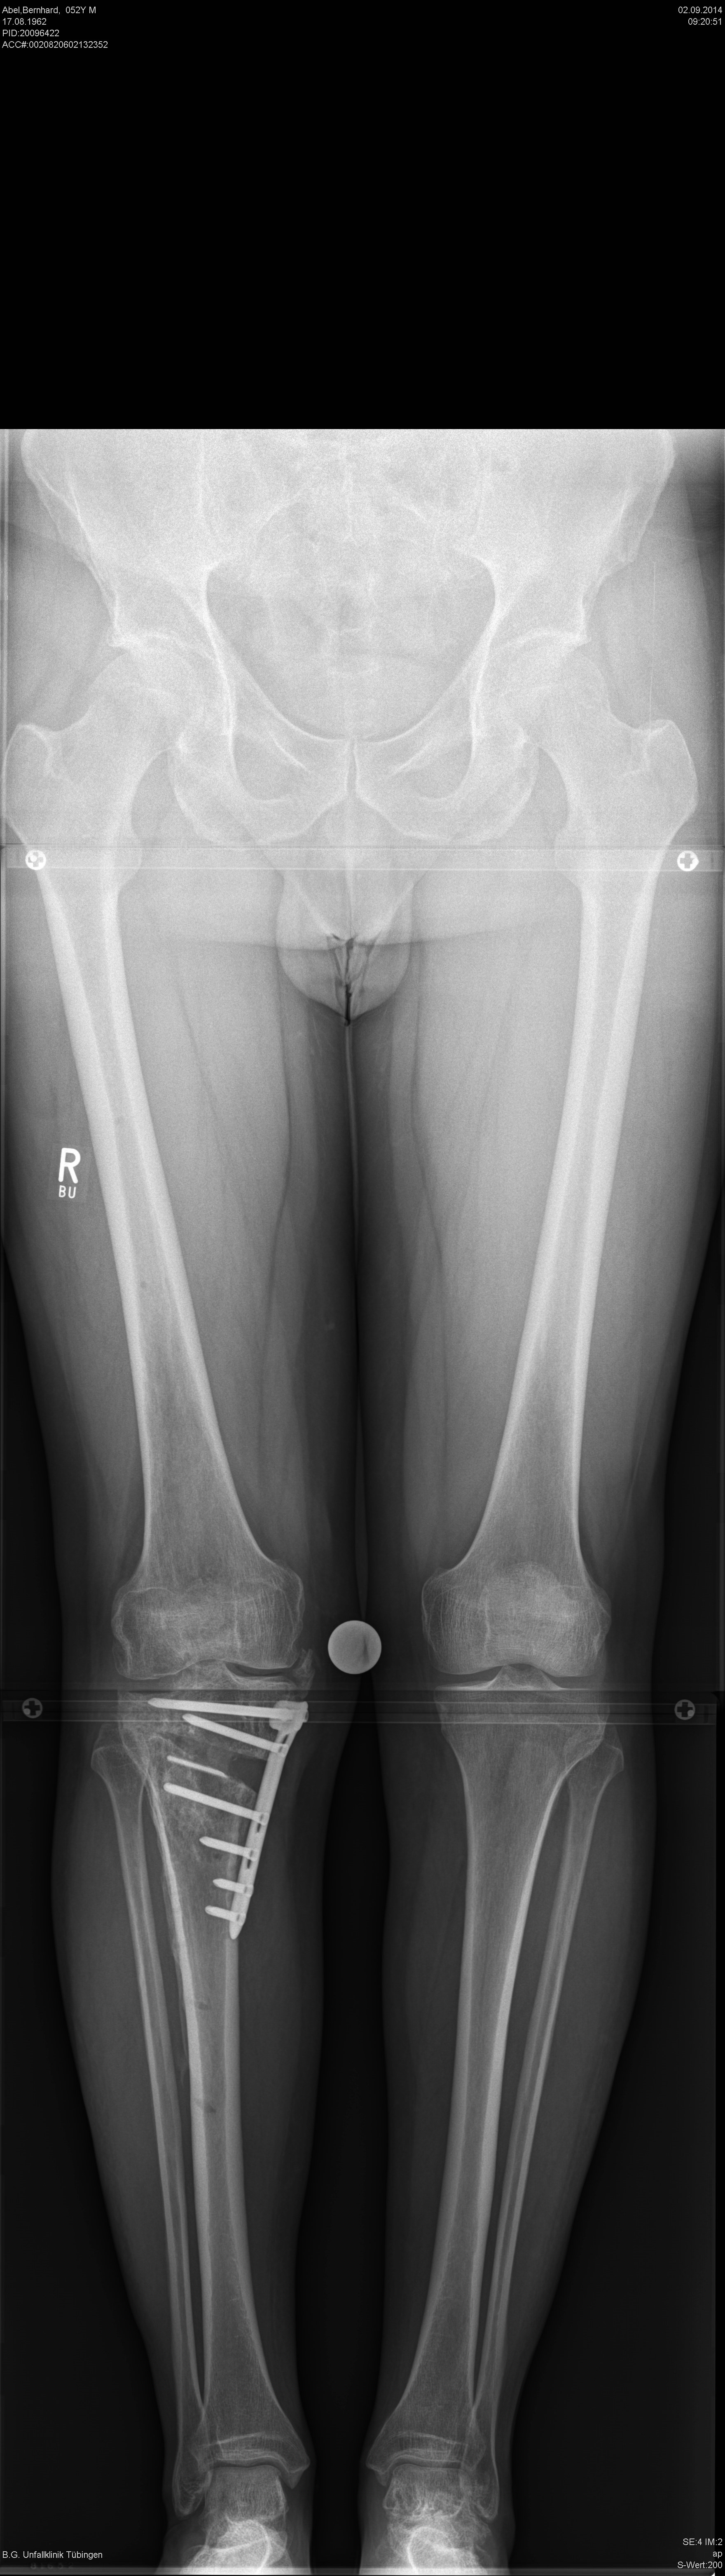

A 52-year-old man with a posttraumatic deformity 2 years after tibial plateau fracture AO/OTA 41C3.3e, PL, PM complained of pain after a normal working day. The patient was a heavy smoker. Activities like sports or hiking were discontinued. Surprisingly ligaments in the coronal and sagittal planes were stable. There was no effusion. Pain was localized in the medial compartment. The range of motion was limited to 0/0/130°. The deformity was corrected with a high tibial osteotomy.

Showcasing a high tibial osteotomy case